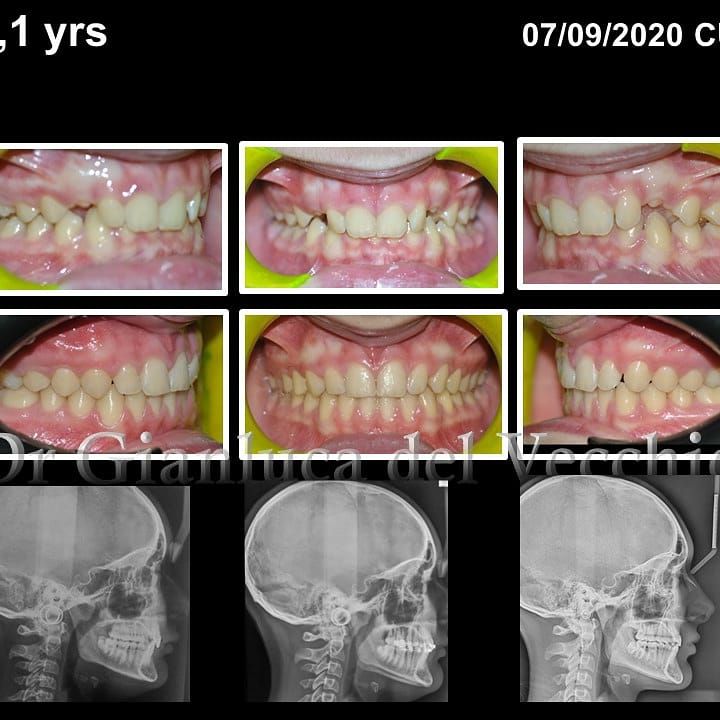

Il dottor Gianluca del Vecchio si occupa esclusivamente di ortognatodonzia, grazie anche alla collaborazione multidisciplinare di una équipe davvero entusiasmante e all’utilizzo di strumenti diagnostici e terapeutici all’avanguardia in ortognatodonzia. Particolare è la sua capacità di condurre i giovani pazienti ad affrontare, nella massima sicurezza emotiva e clinica, qualsiasi eventuale condizione di dolore derivante, ad esempio, da carie o da altre patologie, ma soprattutto di risolvere tutte quelle condizioni di “denti storti”, così spesso causa di disagio psicologico o di fenomeni deprecabili, quale il bullismo.

Queste le ragioni che consentono di trattare le malocclusioni, sia dei bambini che degli adulti, con protocolli scientificamente validati come i più veloci, affidabili e confortevoli.

Il dottore ha acquisito una concezione quanto più pratica e moderna della disciplina e utilizza apparecchietti di diversi colori di tipo mobile e fisso, ma anche terapie sia estetiche che invisibili, fiore all’occhiello di poche realtà in Italia. Per terapie estetiche e invisibili si intendono quelle in grado di spostare i denti, senza che traspaia nulla dalla bocca o con stelline e fili bianchi, esattamente come i denti del paziente.